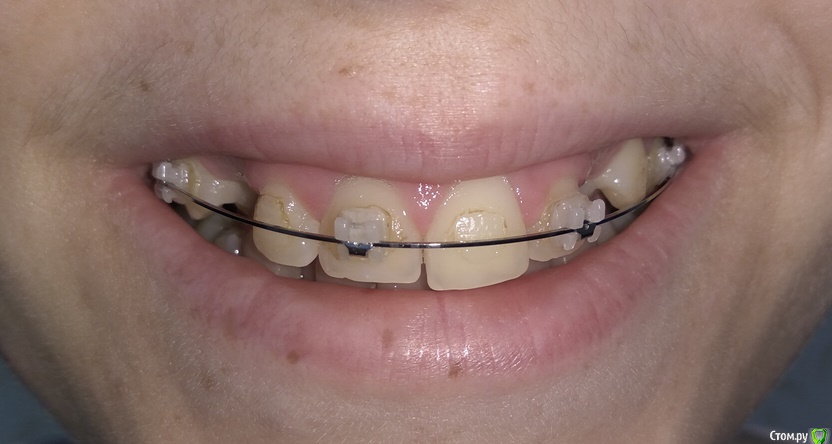

Добрый день. Уважаемые специалисты, прошу совета, БС была установлена в 2015 году, тогда же удалены молочные клыки, ортодонт сказал, что можно вытянуть, но как оказалось не все это могут сделать. Был сделан доступ к постоянным клыкам с небной стороны, приклеены кнопки, установлены лигатуры в области первых премоляров. В 2015-2016 была беременность. Примерно в феврале 2017 лигатуры были заменены на микроимплантаты в области первого моляра с небной стороны и установлены металлические лигатуры. В итоге - движение не наблюдается. Вопрос - можно ли еще пробовать их вытянуть или же делать радикально - удаление и имплантация, или после удаления можно сместить премоляры и моляры вперед?